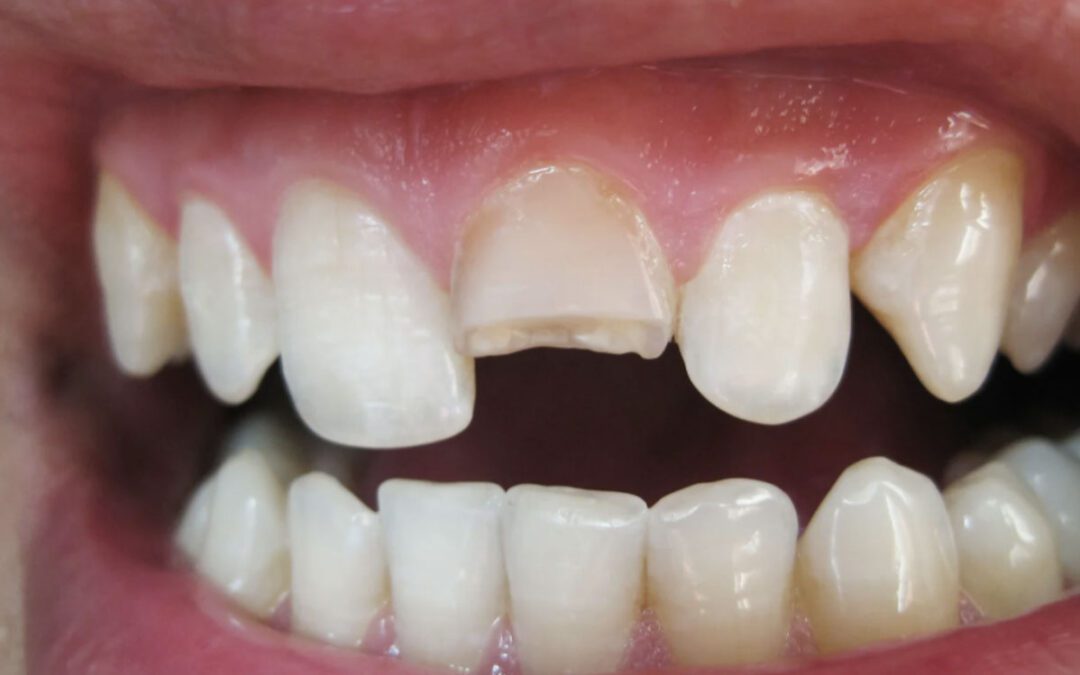

Quando a restauração é indicada?

Nem toda lesão não cariosa precisa ser restaurada. Em casos iniciais, o controle da causa e o acompanhamento podem ser suficientes.

A restauração com resina composta passa a ser indicada quando há:

- Perda estrutural significativa

- Comprometimento estético

- Sensibilidade persistente

- Risco de fratura

A técnica é minimamente invasiva e preserva ao máximo a estrutura saudável do dente. Com sistemas adesivos modernos e um protocolo cuidadoso de acabamento e polimento, os resultados são altamente estéticos e funcionais.